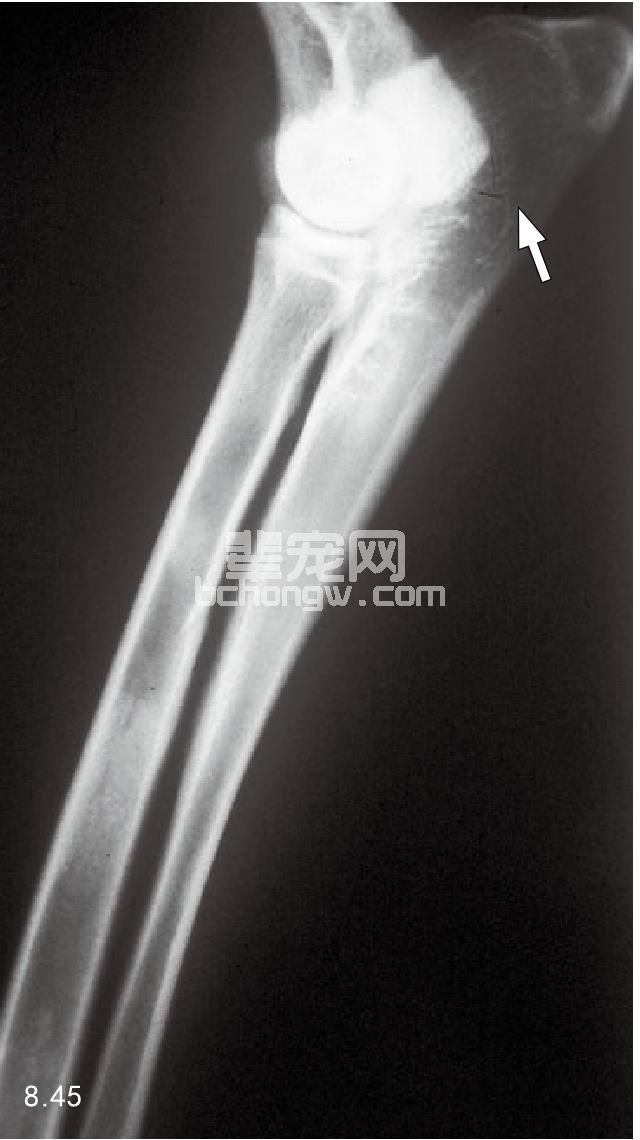

诊断 若X线片显示关节两侧有涉及骨的有害的肿瘤表明为滑液性肿瘤,膝关节与肘关节都是好发的部位 (图8.45)。可通过对与骨有关的软组织损伤的活组织检查来进行诊断。对局部的淋巴结进行细胞学检查也具有 诊断意义。

图8.45 滑液细胞肉瘤、肘部的软组织肿胀和桡骨头侵蚀(箭头所指)。滑液细胞肉瘤最常见于肘关节和膝关节处,肿瘤通常会到关节腔。该病以骨溶 解为主要症状,骨膜增殖较小,软组织矿化很少见。